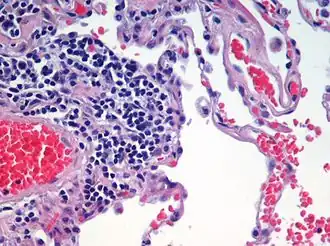

Animal tissue

Animal tissues are grouped into four basic types: connective, muscle, nervous, and epithelial.[6] Collections of tissues joined in units to serve a common function compose organs. While most animals can generally be considered to contain the four tissue types, the manifestation of these tissues can differ depending on the type of organism. For example, the origin of the cells comprising a particular tissue type may differ developmentally for different classifications of animals. Tissue appeared for the first time in the diploblasts, but modern forms only appeared in triploblasts.

Epithelial tissues

The epithelial tissues are formed by cells that cover the organ surfaces, such as the surface of skin, the airways, surfaces of soft organs, the reproductive tract, and the inner lining of the digestive tract. The cells comprising an epithelial layer are linked via semi-permeable, tight junctions; hence, this tissue provides a barrier between the external environment and the organ it covers. In addition to this protective function, epithelial tissue may also be specialized to function in secretion, excretion and absorption. Epithelial tissue helps to protect organs from microorganisms, injury, and fluid loss.